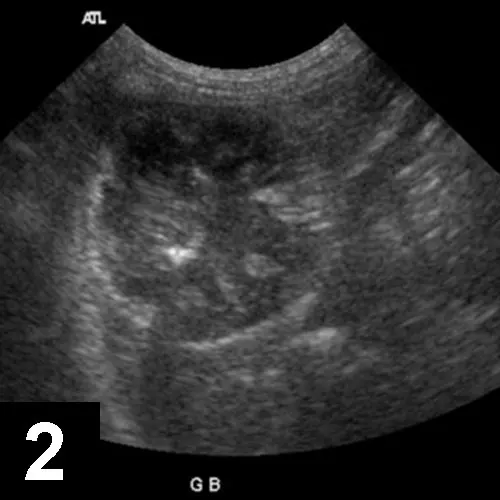

Figure 1A

In this ultrasound, the gallbladder contents show a broad hypoechoic region at the periphery that corresponds to the mucosal layer. The central echogenic bile forms a stellate pattern with a distinct border between the hypoechoic and hyperechoic regions. The gallbladder contents were immobile when the patient was repositioned.